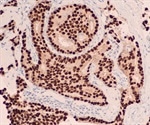

Multi-color Immunohistochemistry (IHC)

Enzymatic Immunohistochemistry (IHC)

Immunohistochemistry (IHC) Imaging Techniques